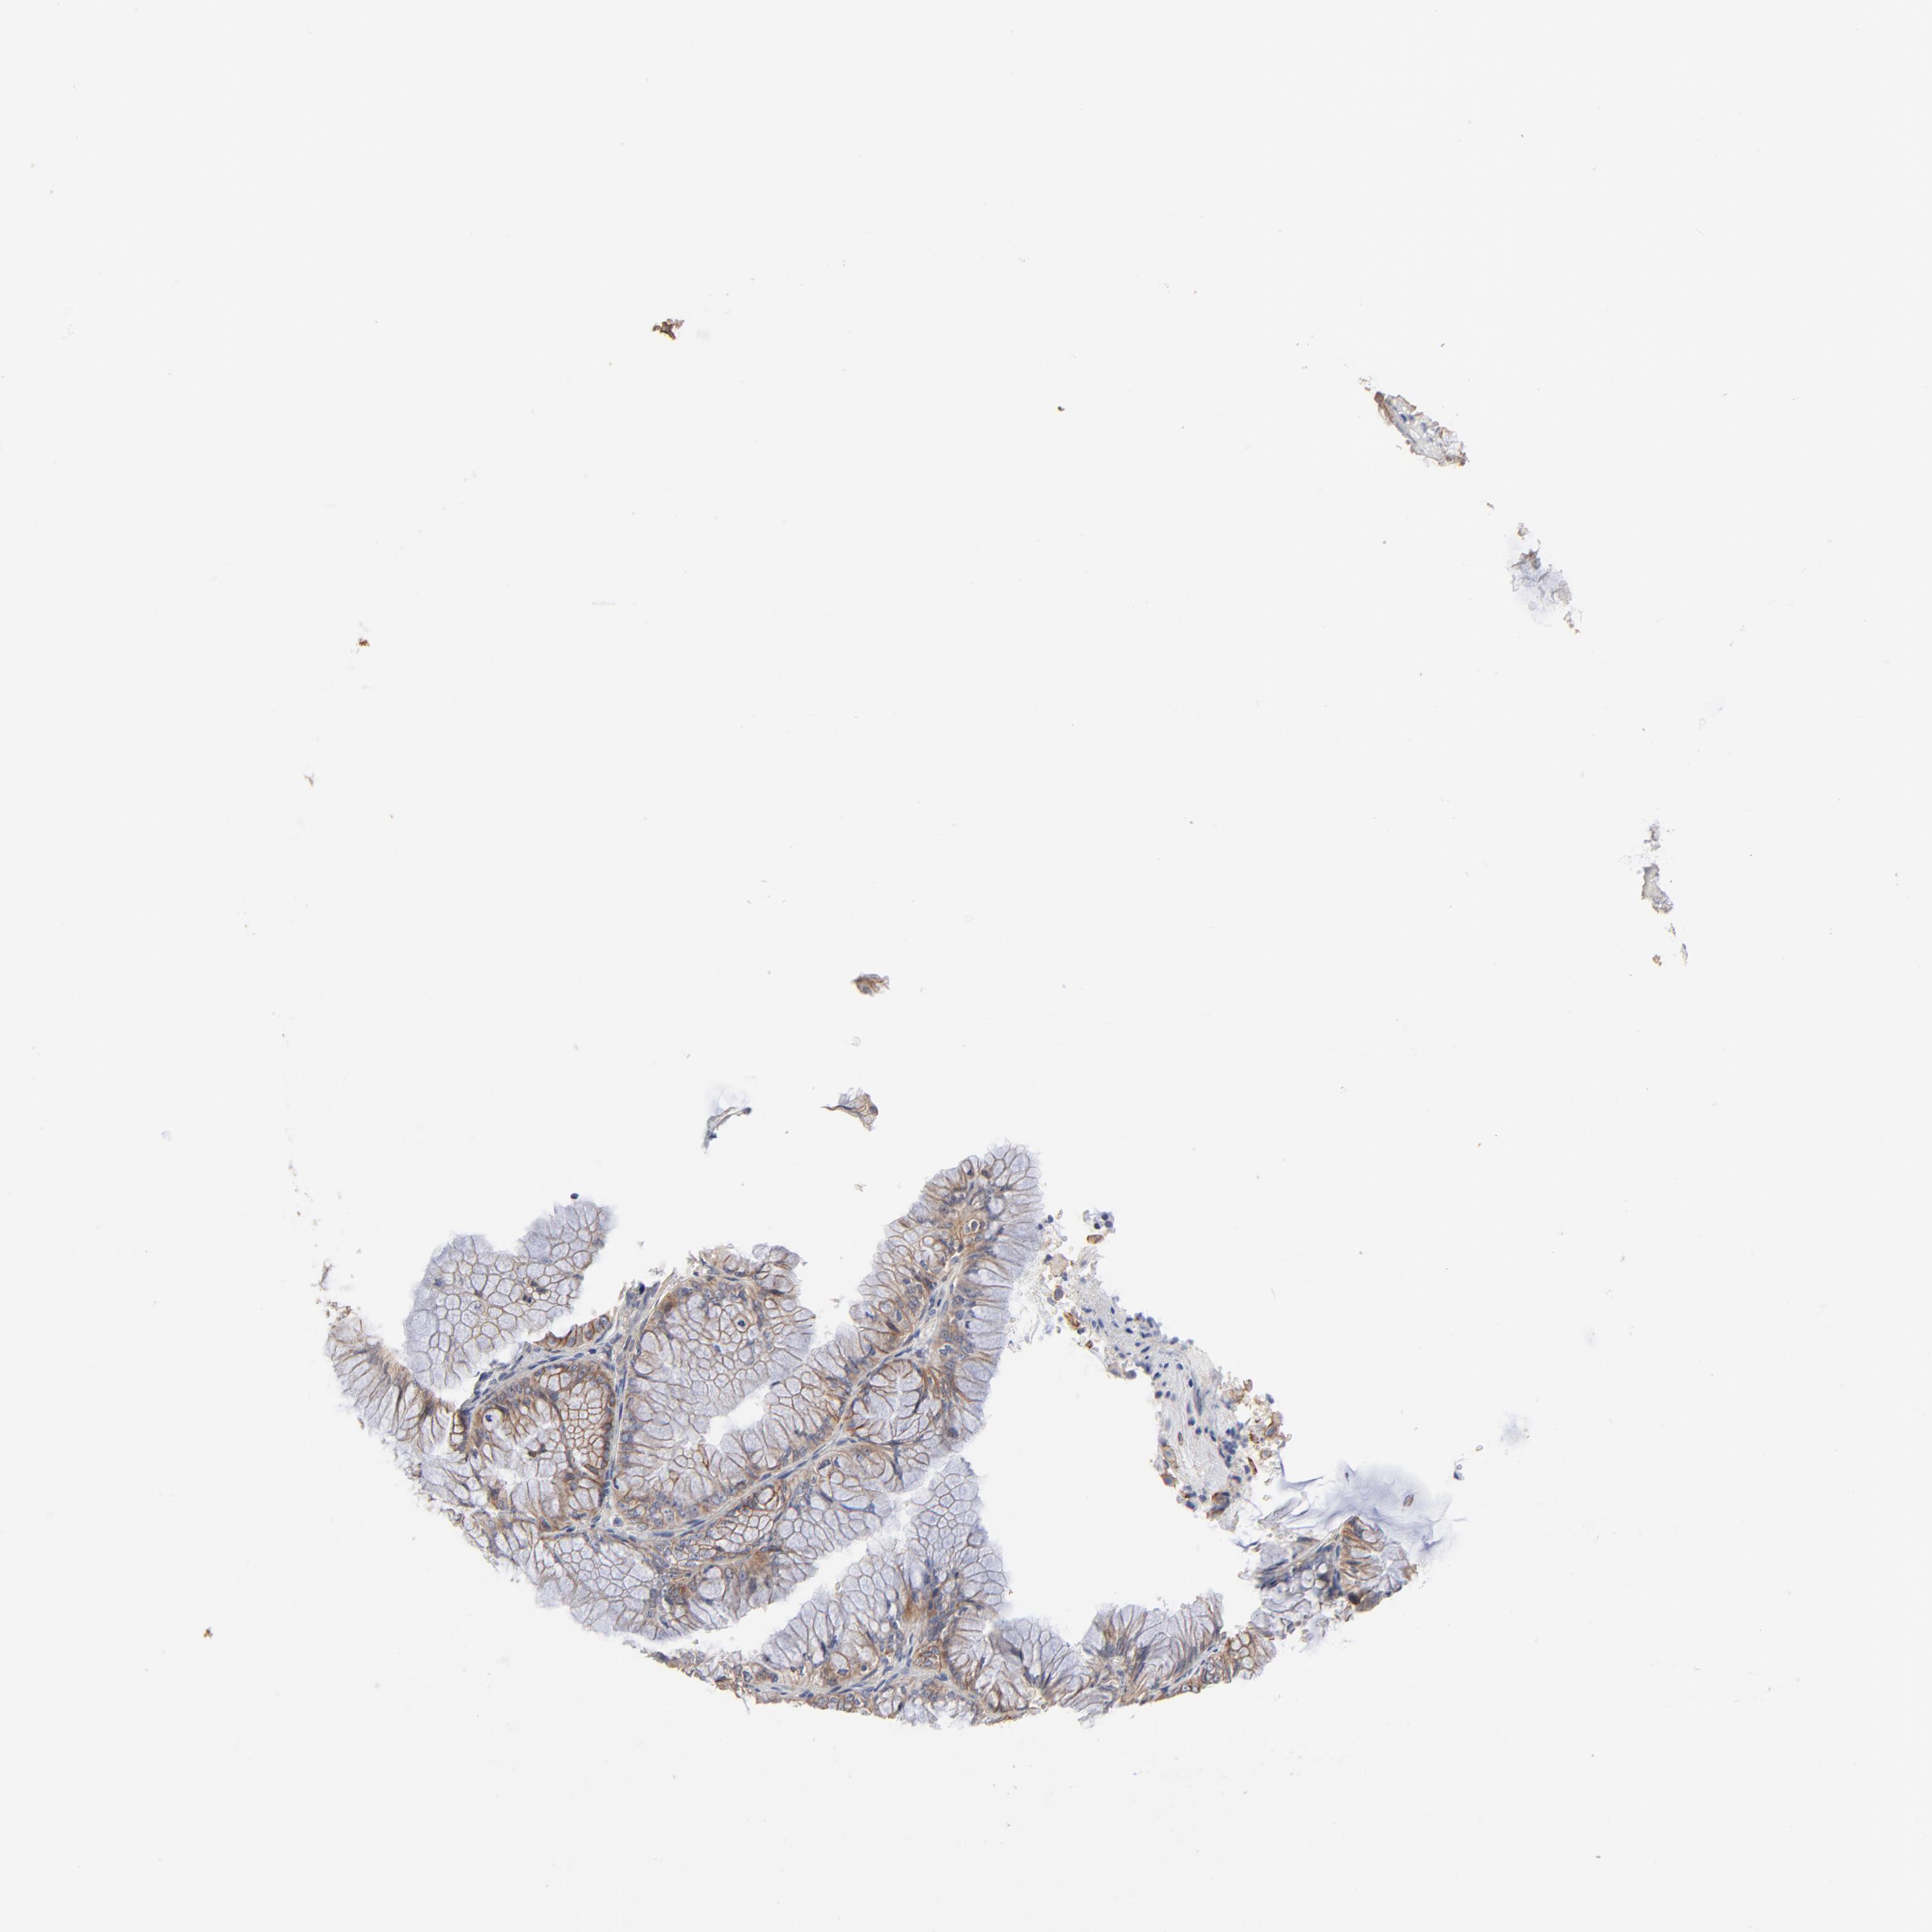

OVARIAN CANCER - Protein expressioni

A mouse-over function shows sample information and annotation data. Click on an image to view it in a full screen mode. Samples can be filtered based on level of antibody staining by selecting one or several of the following categories: high, medium, low and not detected. The assay and annotation is described here.

Note that samples used for immunohistochemistry by the Human Protein Atlas do not correspond to samples in the TCGA dataset.

Antibody stainingi

Antibody staining in the annotated cell types in the current human tissue is reported as not detected, low, medium, or high, based on conventional immunohistochemistry profiling in selected tissues. This score is based on the combination of the staining intensity and fraction of stained cells.

Each image is clickable and will lead to virtual microscopy that enables deeper exploration of all samples and also displays staining intensity scores, fraction scores and subcellular localization as well as patient and tissue information for each sample.

Antibody HPA003324

Staining

High

Medium

Low

Not detected

Intensity

Strong

Moderate

Weak

Negative

Quantity

>75%

75%-25%

<25%

None

Location

Nuclear

Cytoplasmic/membranous

Cytoplasmic/membranous,nuclear

Cystadenocarcinoma, mucinous, NOS

Carcinoma, endometroid

Cystadenocarcinoma, serous, NOS